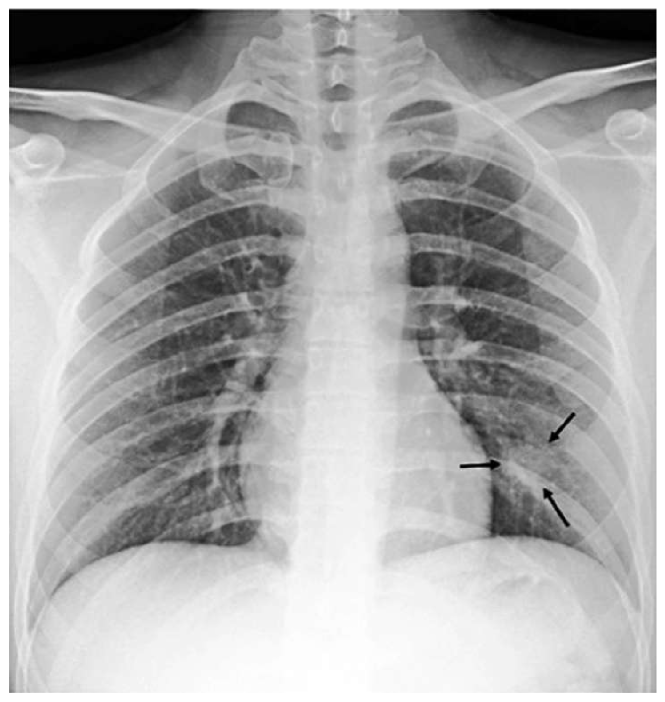

Appendix B More Grad-CAMs of the COVID-CXNet Model with Lung Segmentation Preprocessing

Refer to caption

Figure 21: Grad-CAMs from COVID-CXNet with lung segmentation module